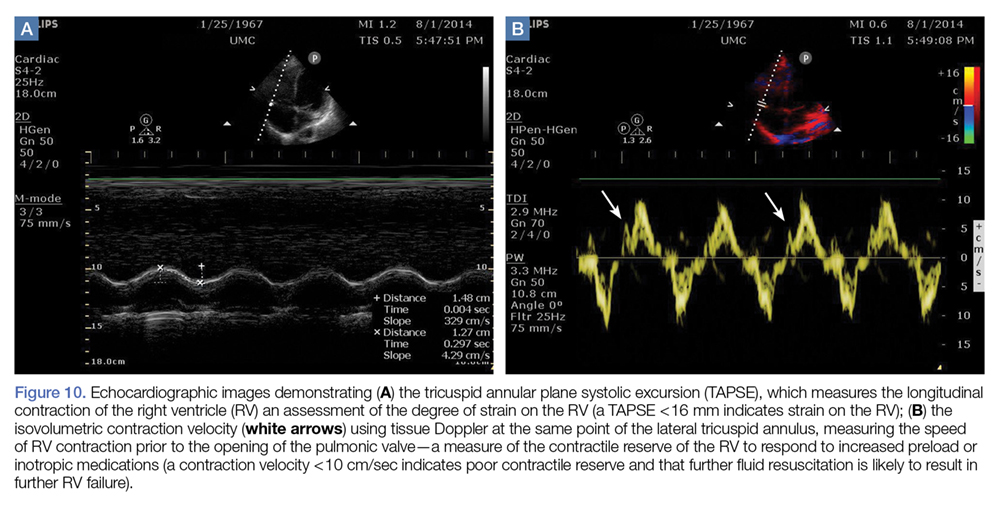

Right Ventricular Strain and Contractile Reserve

Figure 10.

The longitudinal contraction of the RV can be easily measured on bedside ultrasound. In the apical view, M-mode imaging through the lateral annulus of the tricuspid valve will provide a measurement of the systolic movement of the RV. Increased strain on the RV will lead to decreased tricuspid annular plane systolic excursion ( Figure 10a ).38

From the same apical view, tissue Doppler at the lateral tricuspid annulus will give a tricuspid annular peak velocity, a measure of the isovolumetric contraction velocity. This measurement will provide a measure of the contractile reserve of the RV (Figure 10b). A measure of less than 10 cm/sec indicates that further volume and inotropic challenges to the RV will not be effective, and the focus should be to decrease RV afterload with pulmonary vasodilators. 34,39,40